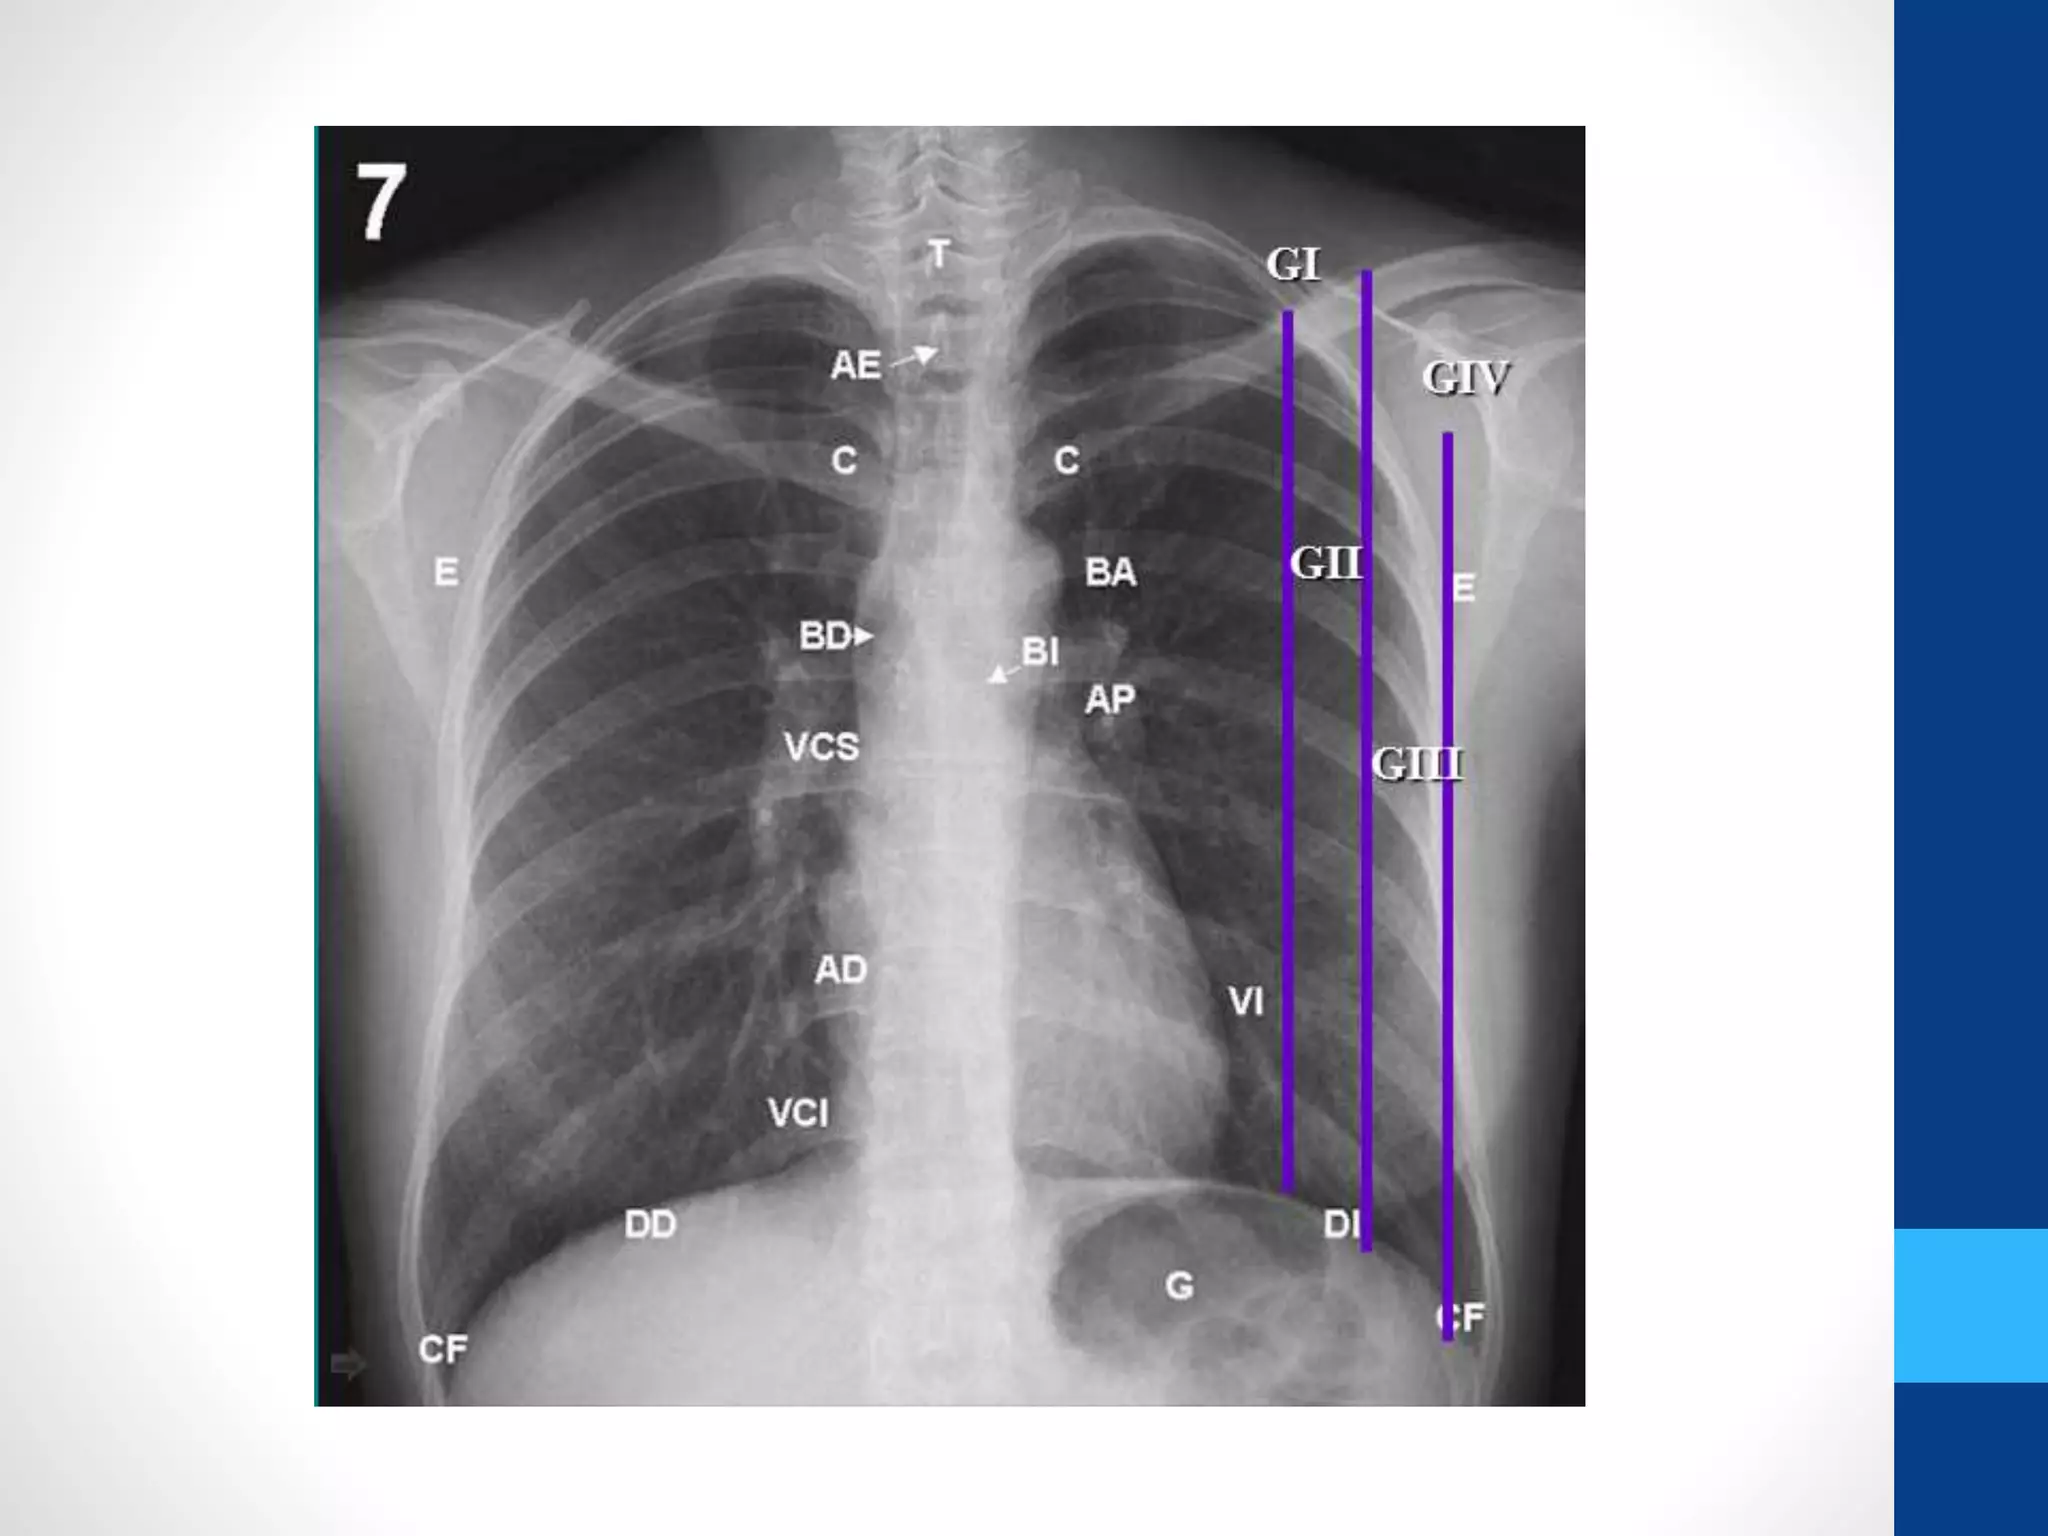

Índice Cardiotorácico | Alejandra Sernaque Herrera | uDocz

Índice Cardiotorácico | Estudiante de radiología, Estudiante de ...

Como medir el índice cardiotorácico (ICT) en la radiografía PA de tórax ...

Índice cardiotorácico (ICT | PDF | Corazón | Medicina Interna

Grados-de-Cardiomegalia-de-Acuerdo-al-ICT.pptx

Índice Cardiotorácico (ICT) - YouTube

Índice cardiotorácico | MARIA SEGURA | uDocz

INDICE cardiotorácico (Cardiomegalia) - YouTube

Índice cardiotorácico - Método y valores normales Sobre la placa ...